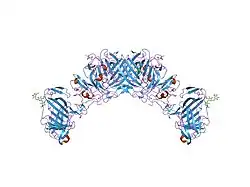

Urokinase is a 411-residue protein, consisting of three domains: the serine protease domain (consisting of residues 159–411), the kringle domain (consisting of residues 50-131), and the EGF-like domain (consisting of residues 1-49). The kringle domain and the serine protease domain are connected by an interdomain linker or connecting peptide (consisting of residues 132–158). Urokinase is synthesized as a zymogen form (prourokinase or single-chain urokinase), and is activated by proteolytic cleavage between Lys158 and Ile159. The two resulting chains are kept together by a disulfide bond between Cys148 and Cys279.[9]

In comparison to the mammalian system, zebrafish (Danio rerio) contains two orthologs of urokinase which have been characterised as zfuPA-a and zfuPA-b. zfuPA-a differs from the mammalian uPA by lacking an exon sequence encoding for the uPAR (urokinase receptor) binding domain; while the zfuPA-b lacks two cysteines of the epidermal growth factor-like domain. zfuPA-b also has no binding activity in fish white blood cells or fish cell lines. The uPAR binding in mammalian system is essential for the activity of urokinase and uPAR as it also functions as an adhesion receptor due to its affinity to vitronectin, integrins and other proteases like PAI-1. The lack of the uPAR binding region in zebrafish uPA, suggests that zebrafish uPA functions without uPAR binding.[10]

The most important inhibitors of urokinase are the serpins plasminogen activator inhibitor-1 (PAI-1) and plasminogen activator inhibitor-2 (PAI-2), which inhibit the protease activity irreversibly. In the extracellular matrix, urokinase is tethered to the cell membrane by its interaction to the urokinase receptor.